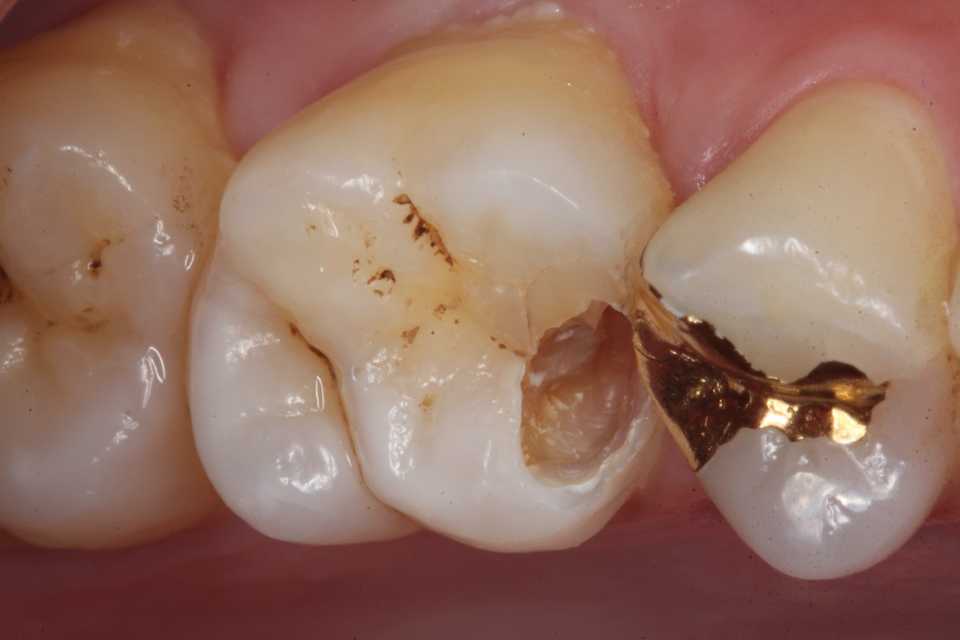

30代男性、右上6、隣接面カリエス、CR充填後(当院ではない)の2次カリエス、外傷性咬合(食いしばり)有り

今日は、10ヶ月程前に時間がないのでα-TCPで仮充填しておいた歯の治療の続き。

とりあえずα-TCPを除去し始めたが内部の象牙質は硬化している。虫歯はα-TCPで治る。

再度3MIX+α-TCPで覆罩してCR充填した。

歯肉縁下に虫歯やクラックが及んでいたができる限り取り除いた。歯肉側のエナメル質は取らざるを得なかったが、これ以上取ると大穴が開く寸前までいった。象牙質のクラックが少し見えるが、α-TCPで治って欲しい。

では時系列でどうぞ

頬側の虫歯は追求するしかない。

こういった歯肉縁下の窩洞はストリップスを使うと出血するだけで上手くいかないだろう。ましてやラバーダムなど歯肉縁下にはかからない。

難しかったので途中経過を撮る余裕がなかった。